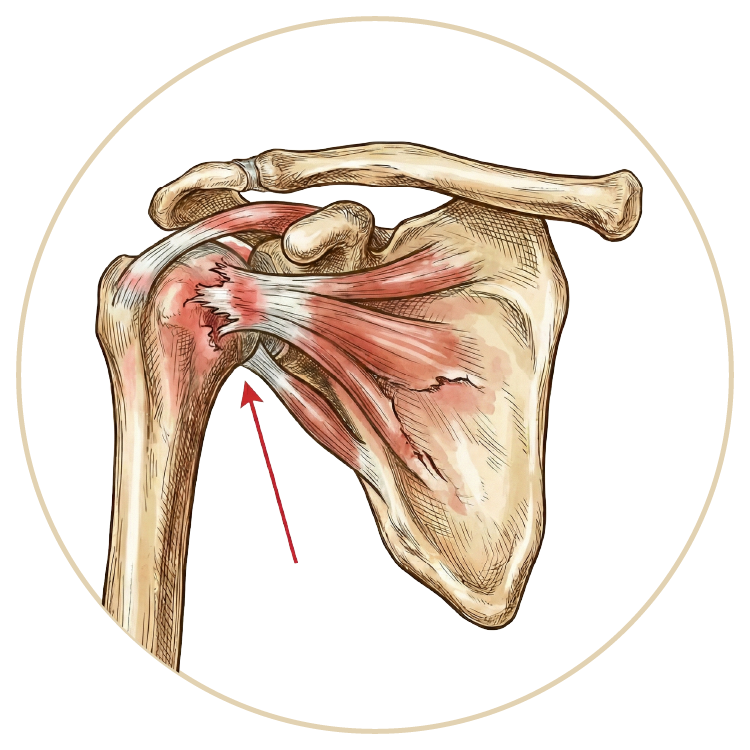

Omuz Hastalıkları ve Tedavileri

Omuz Hastalıkları

Rotator Manşet Yaralanmaları